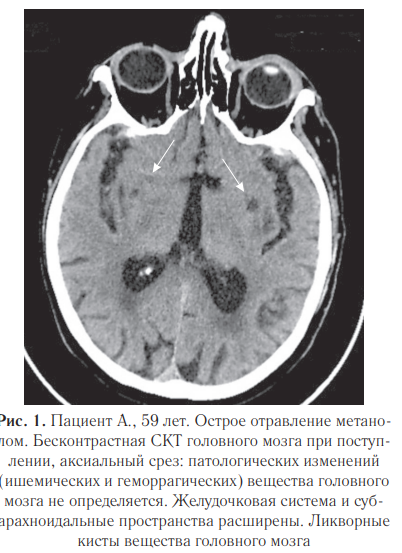

4. Кистозно-атрофические изменения отмечались у 5 (17,8%) пациентов. Пациент А., 59 лет. Поступил в ЦОО ГБУ НИИ СП им. И. И. Джанелидзе с признаками острого отравления метанолом. Диагноз подтвержден при ХТИ: уровень метанола в моче — 2,4 г/л, этанол в моче — 0,7 г/л. Лабораторные показатели при поступлении рН крови 6,818 (норма 7,35–7,45), HCO3 — 3,9 ммоль/л (норма: 22,0–26,0), При контрольном исследовании через 13 дней определяются билатеральные кровоизлияния в вещество головного мозга с прорывом в желудочковую систему (рис. 2).

При проведении судебно-медицинской экспертизы выявлены массивные билатеральные гематомы головного мозга (данные аутопсии представлены на рис. 3), а также инфильтративные изменения в легких с полостями абсцессов (рис.10). Исследования легких: при поступлении (рис. 4), рентгенограмма органов грудной полости (рис. 5) и СКТ груди с реконструкциями в динамике через 1 месяц (рис. 6–8).